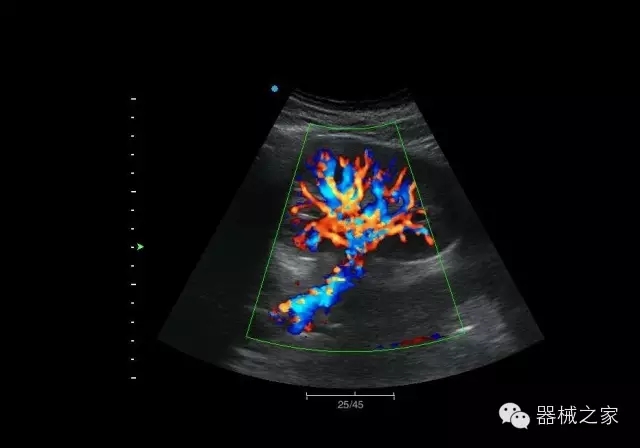

臨床圖片賞析

肝血管瘤